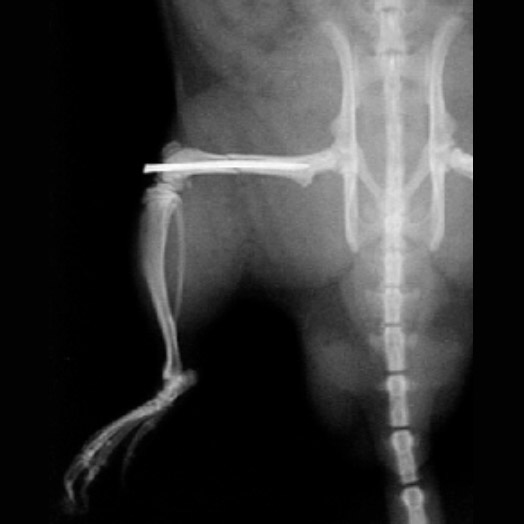

Um dieser Hypothese nachzugehen, ist ein Polytraumamodell in der Ratte mit standardisiertem Thoraxtrauma, hämorrhagischem Schock, einer Femurfraktur und unterschiedlicher Frakturversorgung geplant und genehmigt. Die Ratten werden nach Traumainduktion und Versorgung über einen Versuchszeitraum von 42 Tagen beobachtet. Unter anderem sind Untersuchungen zur Frakturheilung (Mikro-CT, Ganganalysen, histologische Analysen, biomechanische Tests) und der EVs geplant. Die EVs werden zur Analyse der Genexpression osteogener Faktoren isoliert und mit verschiedenen Zelltypen inkubiert.

In der geplanten Studie soll nun die Bewegung der Fibula zur Tibia hin in einem bereits in Vorversuchen entwickeltem Projektaufbau an einem 6-Achsen-Industrieroboter unter kontinuierlicher Belastung und Bewegung schrittweise unter Durchtrennung und Rekonstruktion der Syndesmosenregion untersucht werden (Siehe Abbildung 1). Hierbei wird zunächst ein hinteres Kantenfragment osteotomiert sowie im Folgeschritt eine ligamentäre Durchtrennung des vorderen und interossären Syndesmosenblattes präpariert. Im dritten Schritt wird das hintere Kantenfragment durch eine Plattenosteosynthese rekonstruiert. Gegenübergestellt werden in weiteren Versuchsschritten dann die additive Augmentation des vorderen Syndesmosenblattes mit einem SutureTape Fadenanker im Vergleich zur fibulotibialen Stellschraube sowie die Kombination aus beiden Verfahren bis hin zum Load to Failure Test (Siehe Abbildung 2). Ziele der Studie sind zum einen die Untersuchung der Kinematik der Fibula im physiologischen, instabilen sowie dorsal rekonstruierten Zustand, da erste Ergebnisse auf eine persistierende Rotations- und Sagittalinstabilität der Fibula nach Osteosynthese des hinteren Kantenfragmentes hindeuten. Zum anderen soll die Biomechanik und Stabilität einer neuartigen additiven anatomischen Rekonstruktion des vorderen Syndesmosenblattes im Vergleich zur konventionellen Stellschraube untersucht werden. Unsere Hypothese ist folgende: Die OSG-Kinematik wird durch eine Augmentation des vorderen Syndesmosenblattes mit einem anatomisch verlaufenden Fadenanker im Vergleich zur extraanatomischen Stellschraube physiologischer wiederhergestellt.